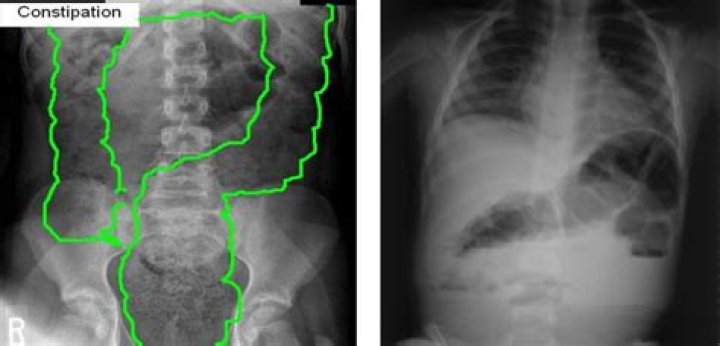

A baby can sometimes get a little stopped up or constipated. In fact, up to 30 percent of children get constipated pretty regularly. This can make your ba...